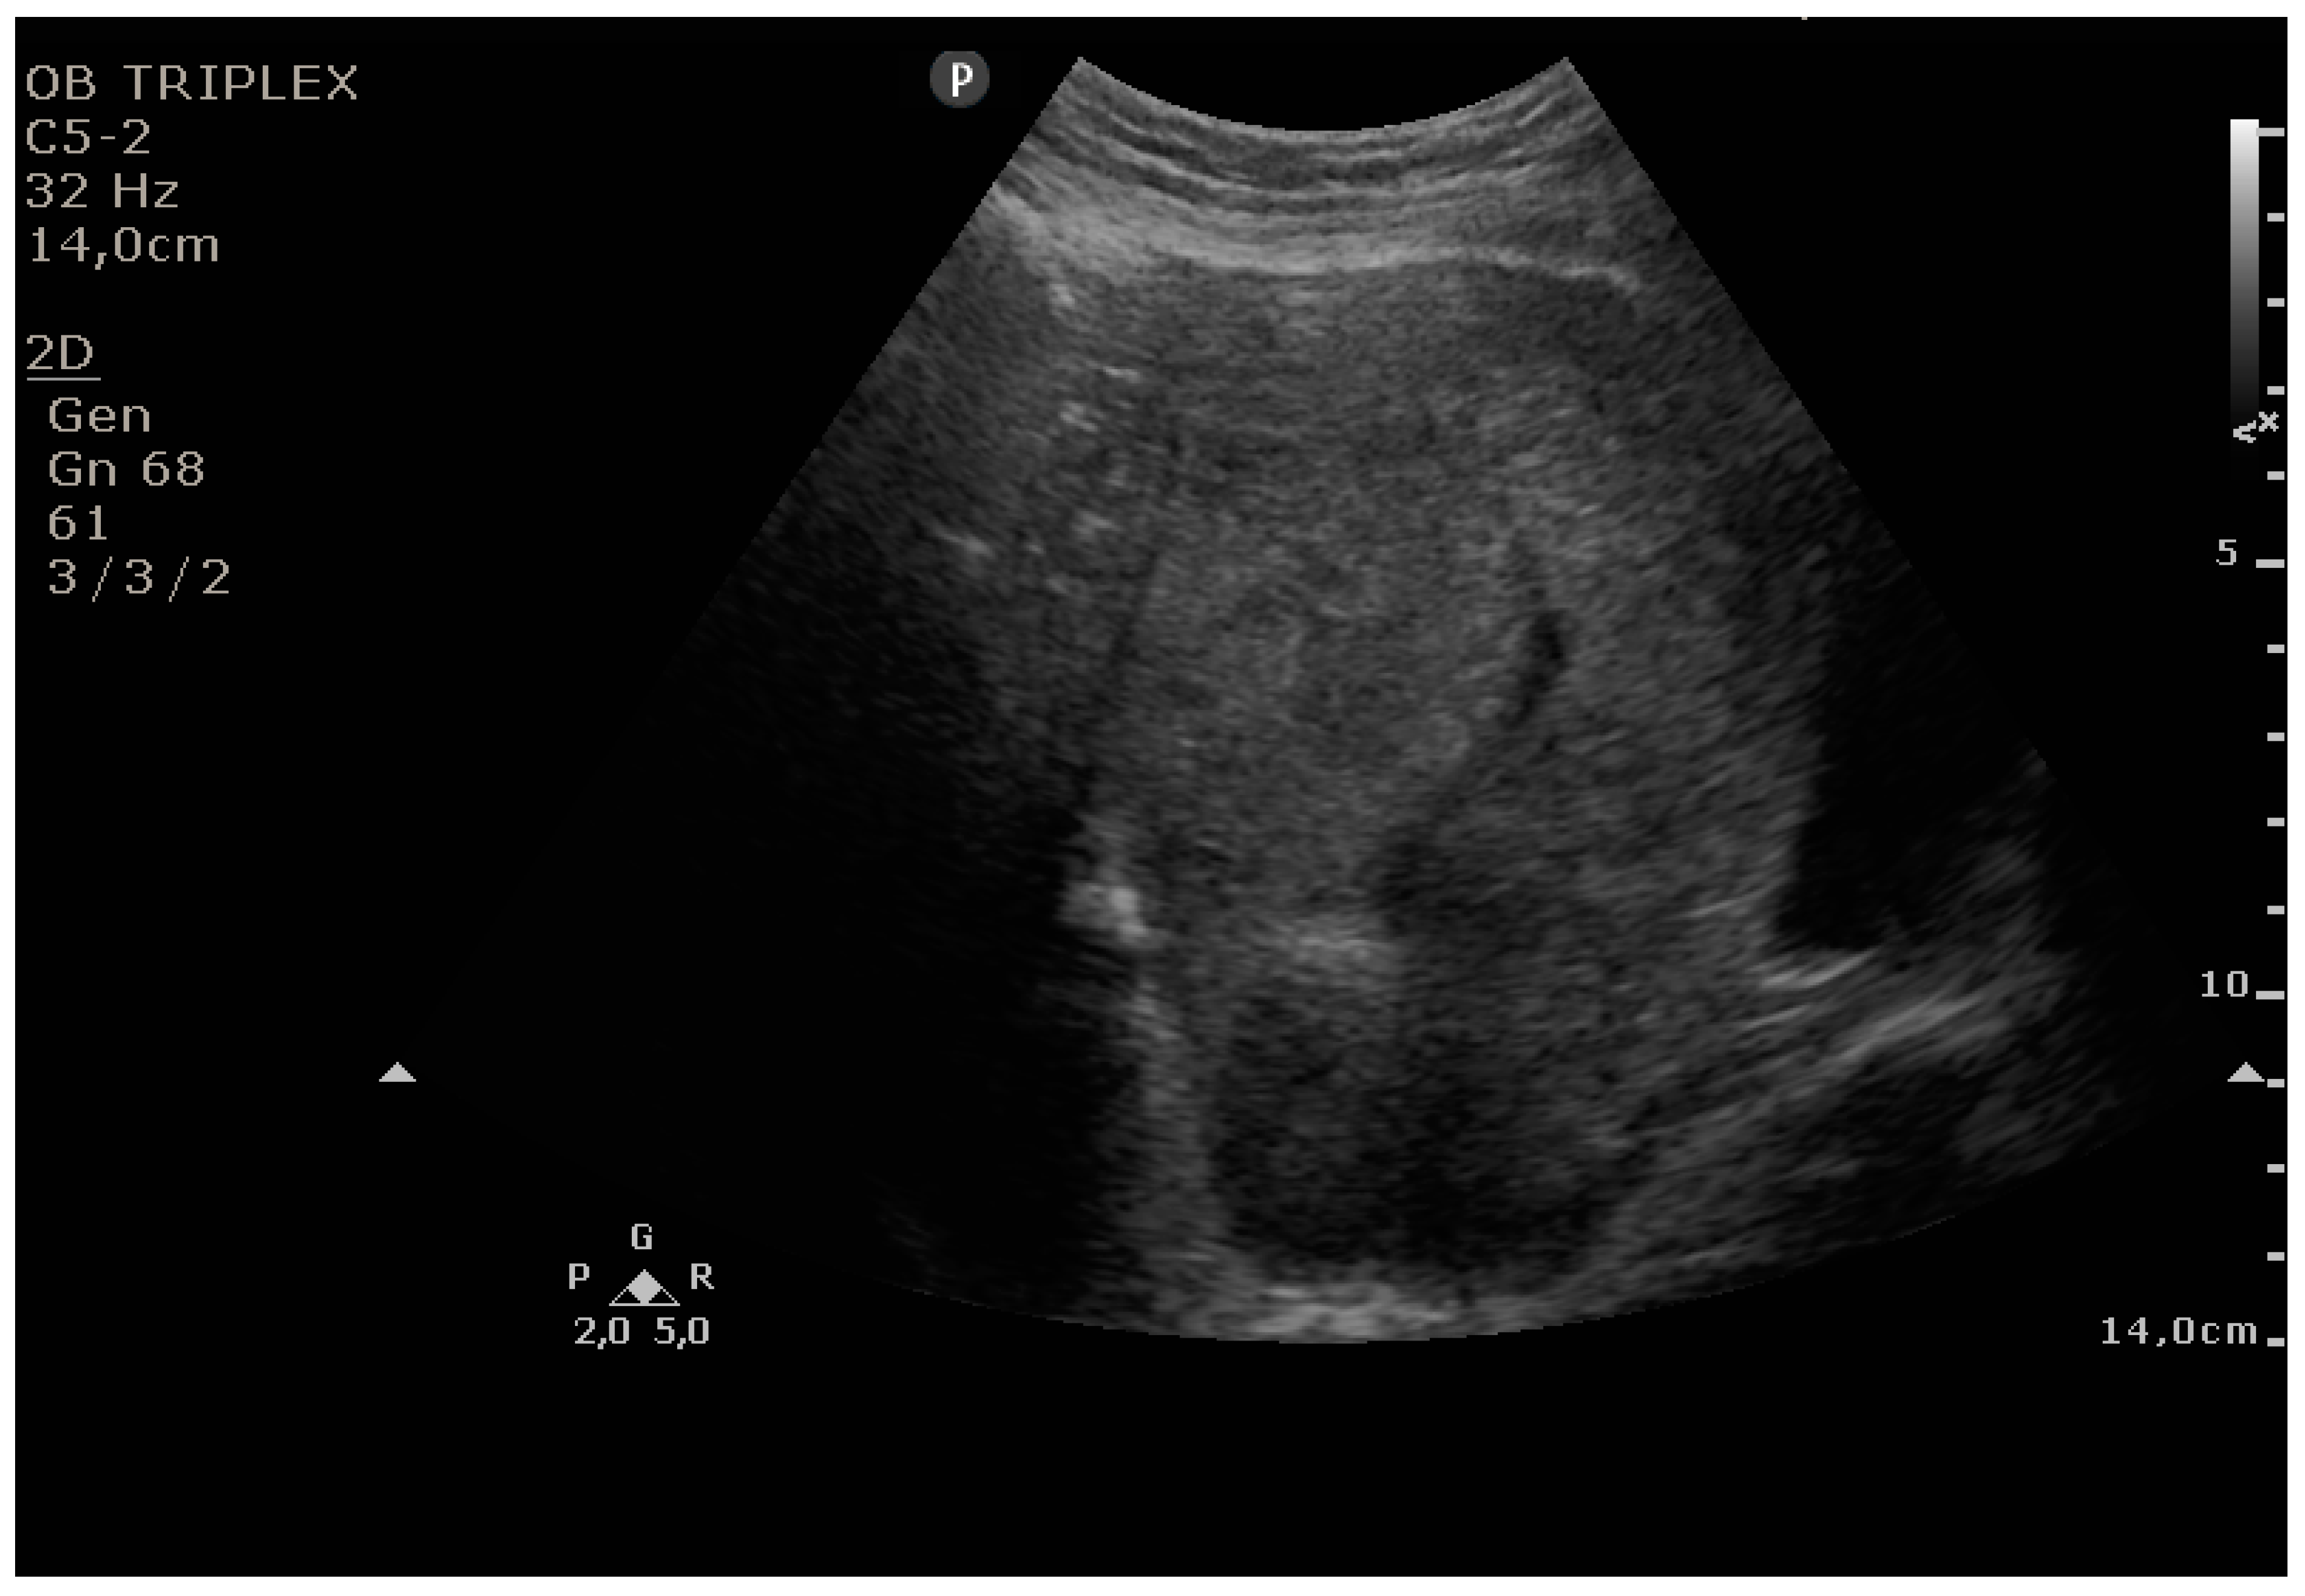

The PUUS method evaluates the proportion of the endometrial length occupied by blood or debris, as follows (Figure 1, Figure 2, Figure 3, Figure 4 and Figure 5):

Figure 4.

Grade 3: less than three-quarters of the endometrial length occupied by blood or debris.